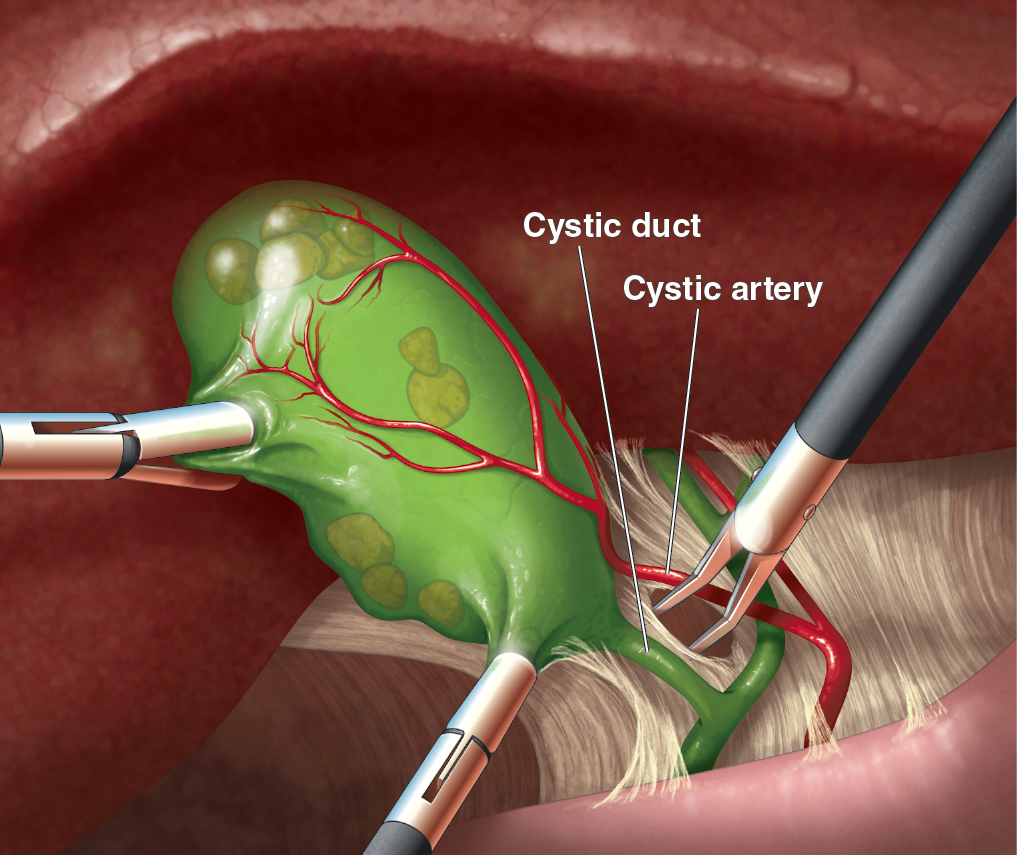

Textbook illustration

I have nearly twenty years of experience in text book publishing, having illustrated books from grade school to graduate level, and in subject areas from human anatomy to biology and geology. I never say no to projects involving dinosaurs.

Patient education

Illustrations can help patients understand surgical procedures they or a loved one are planning to have, or explain how a medication works in the body.